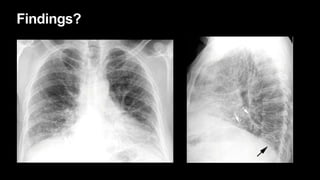

Findings?

USUAL INTERSTITIAL PNEUMONIA AND IDIOPATHIC PULMONARY FIBROSIS

• Most common, 40%

• UIP: histologic pattern, IPF: disease

• Heterogeneous pattern: "spatial" and "temporal“ heterogeneity

• >50 yrs

• progressive dyspnea, cough, weight loss, and finger clubbing

• PFT: restrictive pattern